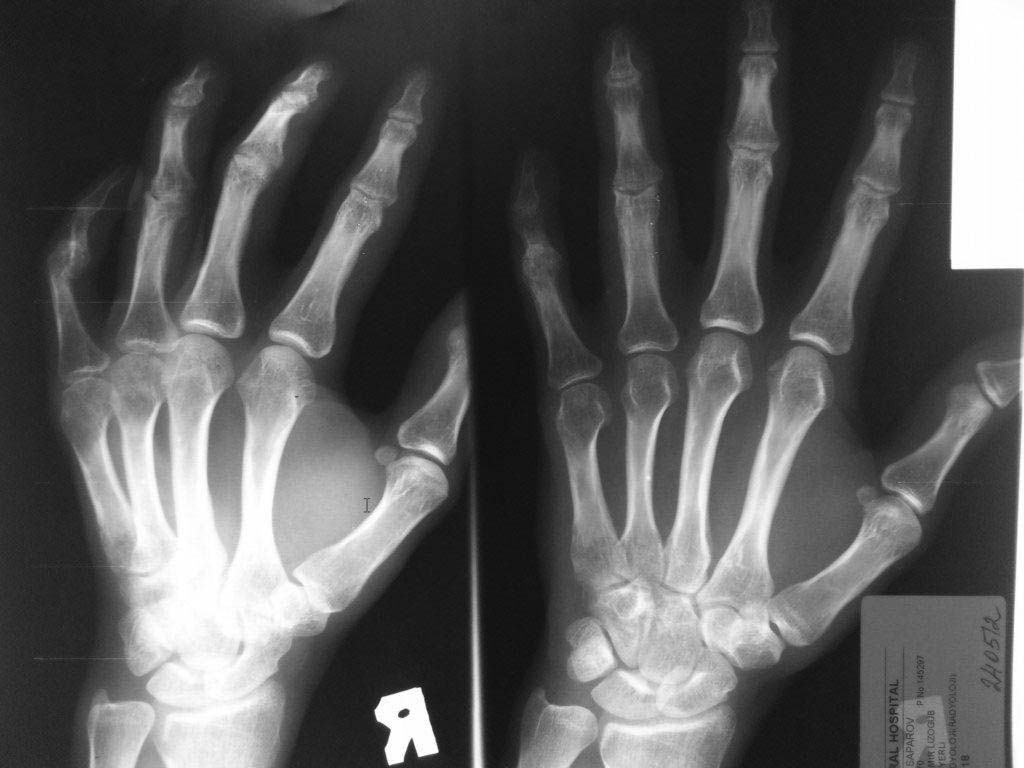

Уважаемые Коллеги! Помогите разобраться с диагнозом, из анамнеза молодой человек 27 лет, порезал руку ножом в области 4 и 5 пальцев правой кисти,

в виду особого состояния (запой), только через 2 месяца обратился в одно из травмотделений с резаной раной 4,5 пальцев правой кисти и полным разрывом сухожилий сгибателей, где был произведен неудачно поздний вторичный шов сухожилий сгибателей, после операции стойкая сгибательная контрактура этих пальцев.

Далее он обращаеется в другое травм отделение где просит врача выпрямить ему эти пальцы, что врач и сделал (артродез межфаланговых суставов в нефункциональном положении, а полностью разогнутом, прямом). После этого начинается самое интересное - уже ровно год после этих событий непрекращающее гноетечение из свищей 4 пальца на уровне проксимальной-средней фаланги.

Ему 4 раза в поликлинике и в одном из хирургических стационаров лечили консервативно и оперировали безуспешно от костного панариция.

Когда обратился ко мне на уровне средней фаланги 4 пальца, свищ по ладонной поверхности, типично как при костном панариции (остеомилите фаланги), но когда я посмотрел на снимок костей, то не увидел остеомиелита, небольшой остеопороз, но он не может быть начальным проявлением остеомилита фаланги, так как является временным переходным состоянием секвестрации фаланги и длится не более 2 недель при отсутсвии лечения, а с момента артродеза прошел уже год.

Наводит на мысль про хронический гнойный тендовагинит, но разве так долго может длиться процесс суставного панариция, да и неужели только я не вижу остеомилита? Прилагаю фото и рентгенограмму больного. Если тендовагинит, тогда буду проводить или проточно-промывное дренирование или же ваккумное дренирование после ревизии пальца, сам больной так устал, что просил ампутировать палец.